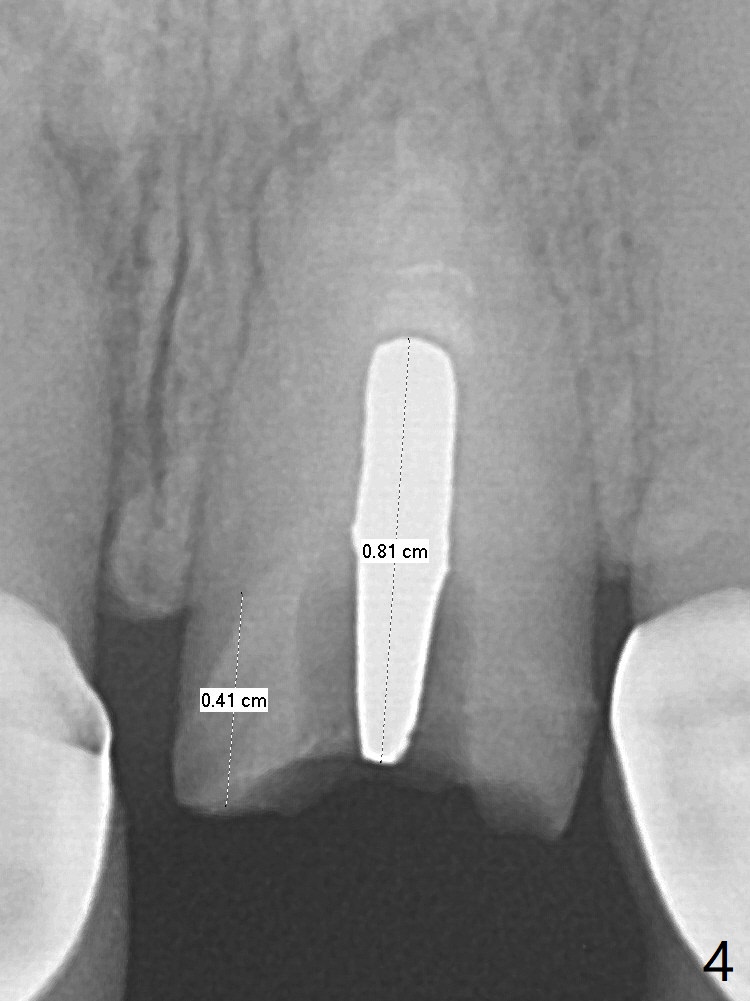

A 51-year-old woman with poor dentition has history repeated dislodged crown and post at #9. Finally the post fracture (Fig.1). After discussion of treatment options, she chooses to save the tooth. Treatment plan is to remove post, possible RCT retreatment, redo post and crown. The post remains stable following lengthy use of Piezo scaler (Fig.2). It appears that Piezo is quite aggressive, removing the tooth structure and the metal. Finally the coronal portion of the post is removed for cast post (Fig.3). There is approximately 2 mm for ferrule effect (Fig.4). The cast post is cemented with RelyX Ultimate and prepared for crown (Fig.5-7).